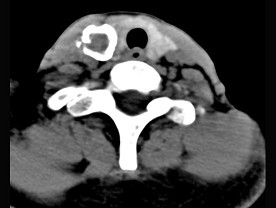

5.男性,40岁,颈部出现无痛性囊性包块2年余,CT扫描如图所示,最可能诊断为  (    )

正确答案:A